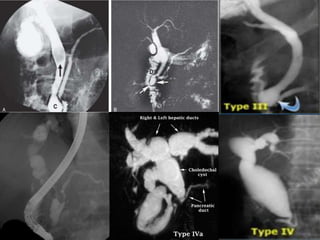

Choledochal Cysts

Choledochal cysts are congenital cystic dilatations of any portion of extra hepatic

bile ducts, most commonly the main portion of CBD.

It is postulated that this condition begins with an anomalous junction of the

common bile duct and pancreatic duct proximal to the duodenal papilla.

Higher pressure in pancreatic duct combined + an absent ductal sphincter allows

free reflux of enzymes into biliary tree, weakening wall of the common bile duct.

Normal Abnormal

Diagnosis of a choledochal cyst is made on the basis of disproportional

dilatation of the extrahepatic bile ducts after excluding the possibility of

a tumor, stone, or inflammation as the cause of the dilatation.

The estimated incidence of choledochal cysts in Western countries varies

between 1 in 100,000 and 1 in 150,000 individuals.

The rate of incidence is higher in Asia and occurs more frequently in

women (M: F- 4:1).60% of patients present before age 10, although

choledochal cysts can present from birth to old age.

This anomaly is associated with increased incidence of GB anomalies,

biliary anomalies ( stenosis /atresia), and congenital hepatic fibrosis.

Complications of choledochal cysts in adults include rupture with bile

peritonitis, secondary infection (cholangitis), biliary cirrhosis and portal

hypertension, calculus formation, portal vein thrombosis, liver abscess,

hemorrhage, and malignant transformation into cholangiocarcinoma.

Todani classification

Newborns and infants present with obstructive jaundice.

Older children and adults may have the classic triad of right upper

quadrant pain, intermittent jaundice, and a palpable right upper

quadrant mass.

In adult patients, a choledochal cyst is often first diagnosed on cross-

sectional imaging.

CT and ultrasound demonstrate a fluid-filled structure beneath the

porta hepatis separate from the gallbladder that communicates with the

hepatic ducts.

An abrupt change in the caliber of the ducts occurs at the site of the

cysts.

Intrahepatic ductal dilatation may be present as well.